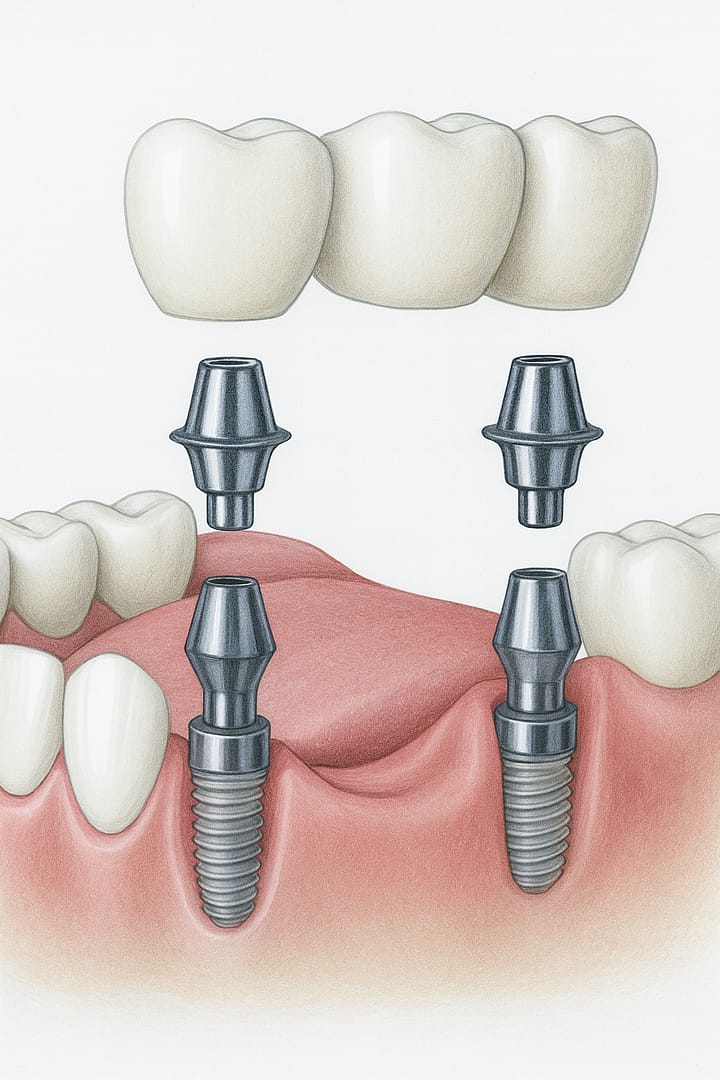

Puente fijo sobre implante

Dos implantes dentales sostienen un puente formado por 3 o más coronas unidas entre sí. Es la solución ideal cuando hay varias piezas consecutivas ausentes, sin necesidad de colocar un implante por cada diente.